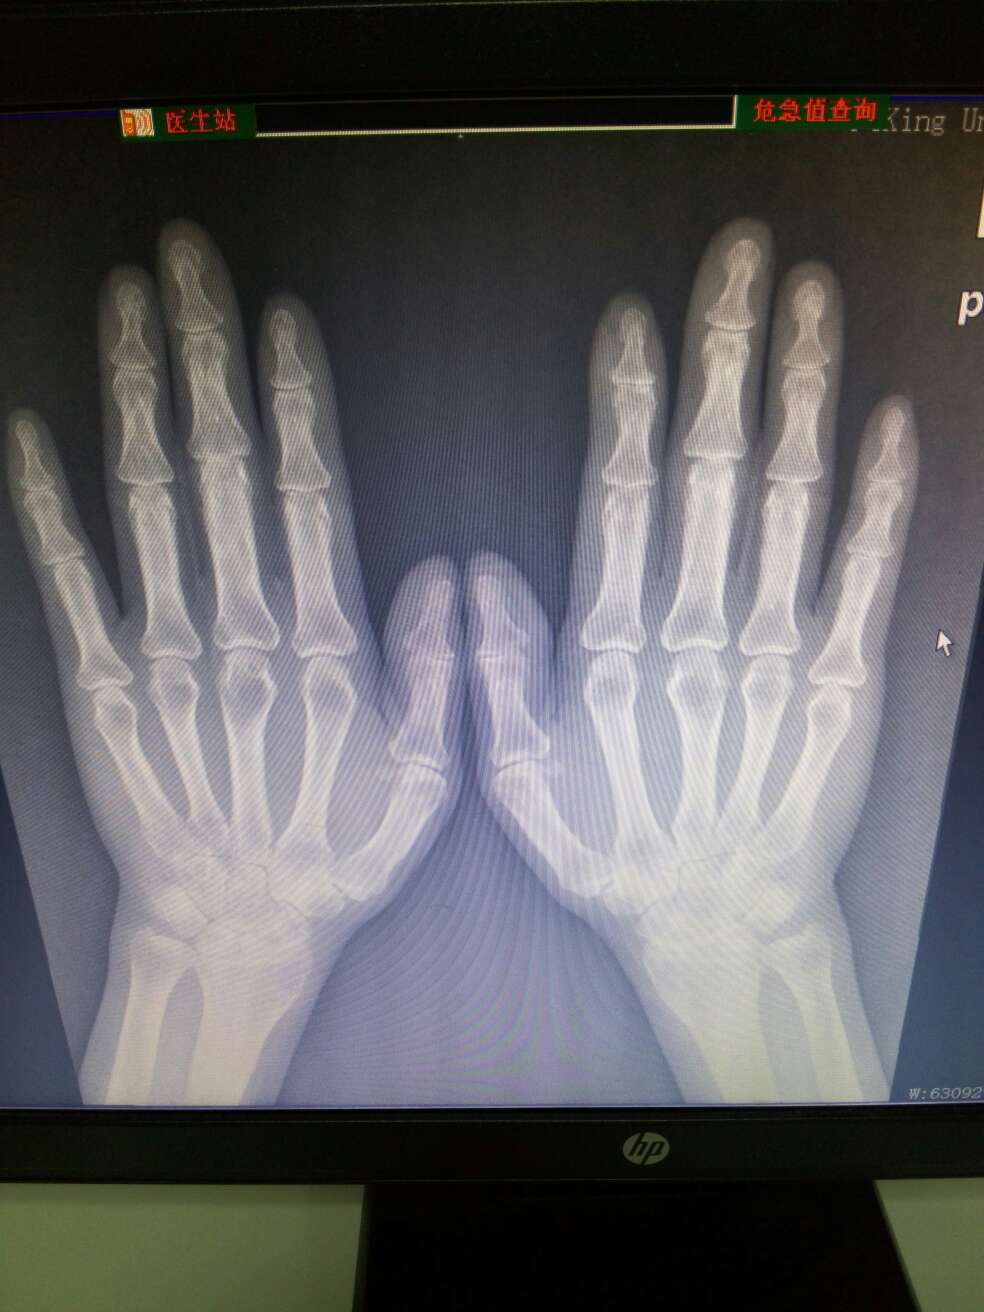

类风